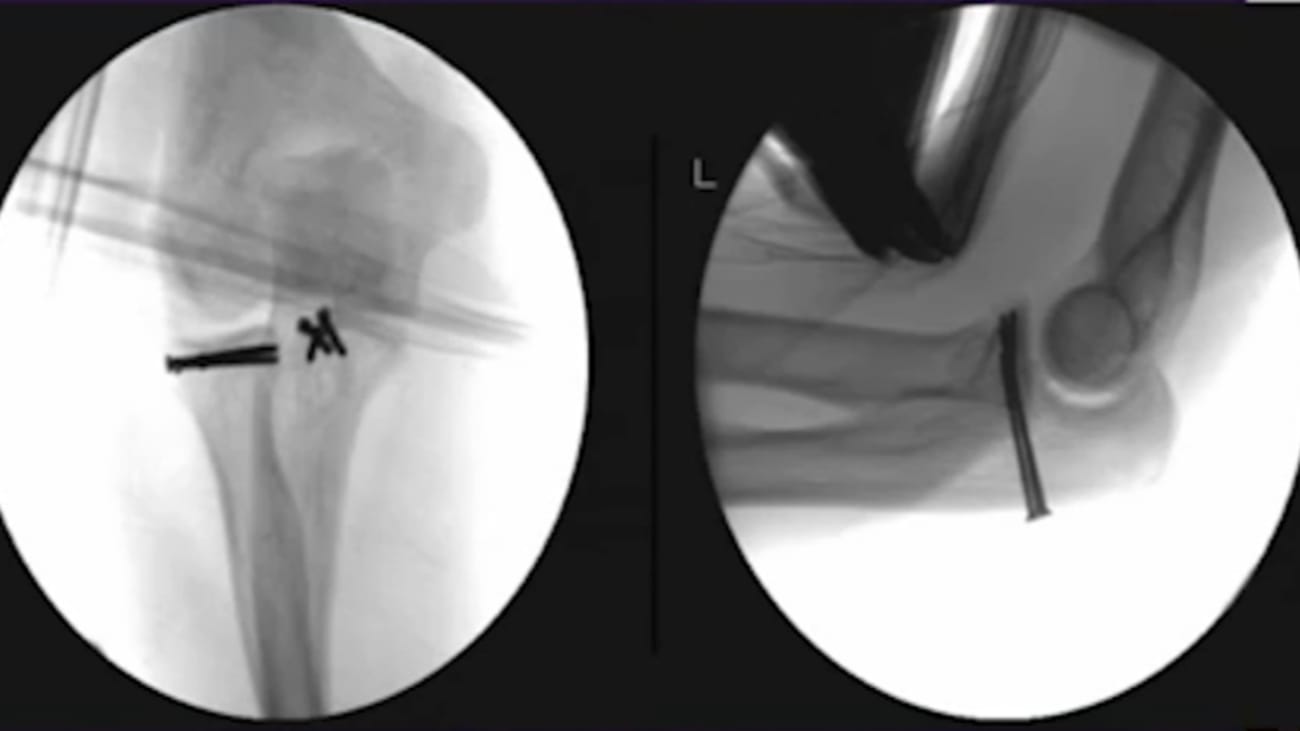

Part 2: Terrible Triad Injuries and the Complex Elbow: In a Terrible Triad, What should be fixed first?

Terrible Triad Injuries and the Complex Elbow: Current Concepts